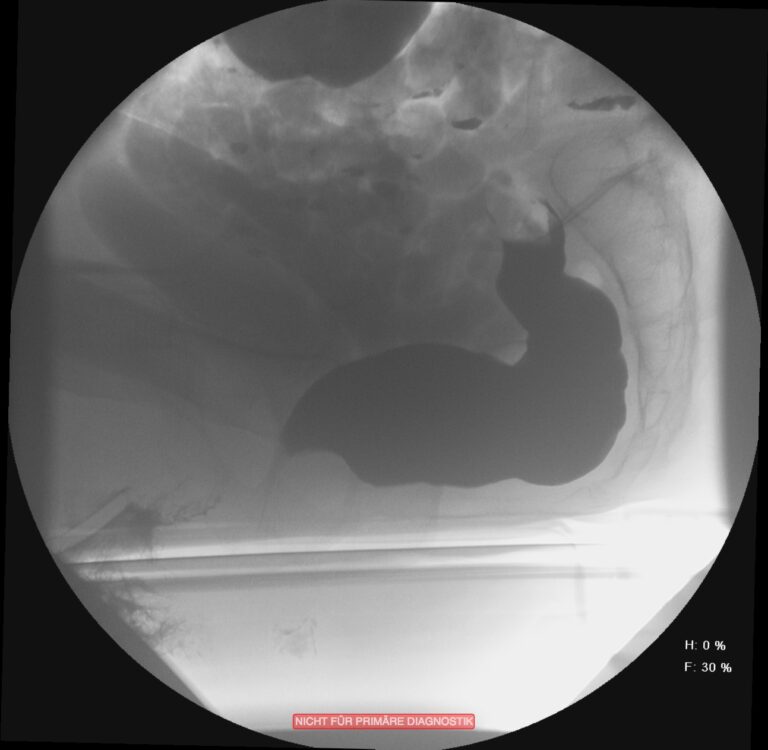

In vielen Fällen ist diese Obstruktion mit einer gleichzeitig bestehenden Inkontinenz kombiniert. Dies erscheint auf den ersten Blick etwas paradox. Durch die andauernde unvollständige Entleerung ist die Rektumampulle aber nie vollständig geleert und der Schließmuskelapparat durch die ständige Überdehnung des Beckenbodens nicht in der Lage, den Stuhlgang immer suffizient zurückzuhalten. Zur Differentialdiagnostik werden Sphinktermanometrie, Endosonografie, Rektoskopie und ein Röntgenverfahren, die Defäkografie angewendet. Diese erlaubt eine Darstellung der funktionellen Abläufe und anatomischen Veränderungen während der Defäkation. Das Ausmaß der Obstruktion und der Inkontinenz wird mit anamenstischen Score-Werten objektiviert.